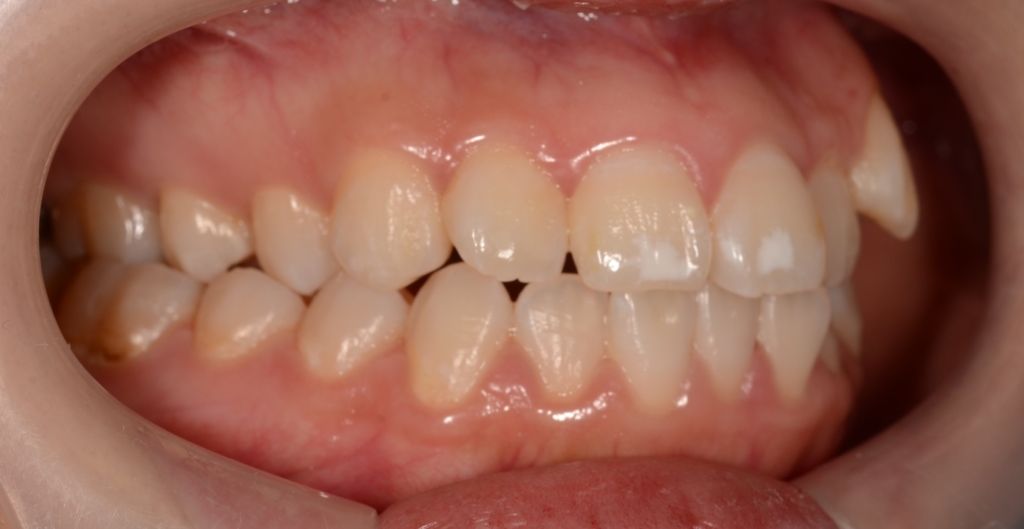

【Before】

#1.上下顎前突

#2.歯と顎の不調和による叢生(軽度)

と診断しました。